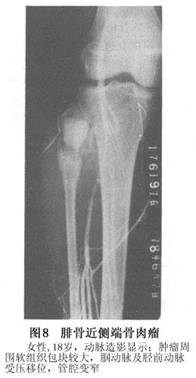

有助於顯示腫瘤的骨外部分以及血管被移位的程度;但是其用於診斷和鑑別診斷的價值卻是有限的,可以提供骨外的腫瘤部分的輪廓,以及腫瘤周圍血管受壓情況(圖8)。近年來我們採用了選擇性血管造影及數字減影等新技術。可以通過導管只選擇供應腫瘤的血管造影,並通過數字減影將周圍骨組織減去、因而可將腫瘤局部血液供應情況顯示清楚。不僅爲術前估計術中出血情況提供了分析依據,而且通過導管可用明膠海綿將供應腫瘤的主要血管堵塞,使腫瘤區之血運大爲減少,由於這種臨時性堵塞可持續3天,故3天內如行手術則可大大減少失血。如果腫瘤不能切除,則永久性栓塞對抑制腫瘤發展有一定作用。